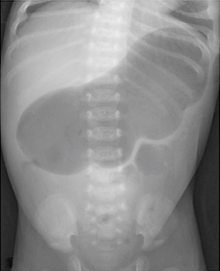

In infants under one year of age, the normal gas pattern on an abdominal X-ray appears honeycomb or polygonal shaped throughout the abdomen (Figure 1).3,4

Figure 1 Anteroposterior supine radiograph in a normal neonate on day-3 of birth showing honeycomb or polygonal gas pattern throughout the abdomen with gas visible in the rectum. It is difficult to differentiate small from large intestine in the neonatal period.